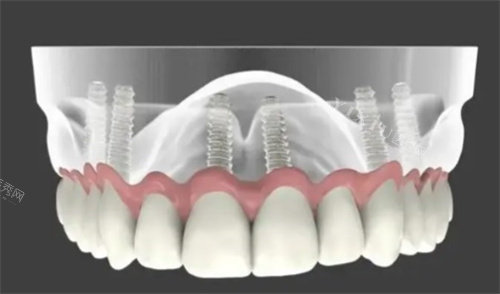

一、种植牙价格参考

(含CBCT+种植体+基台+金属冠,质保5-10年)

即刻负重/全口半口种植:现场评估后一口价,单颗再减200-400元。